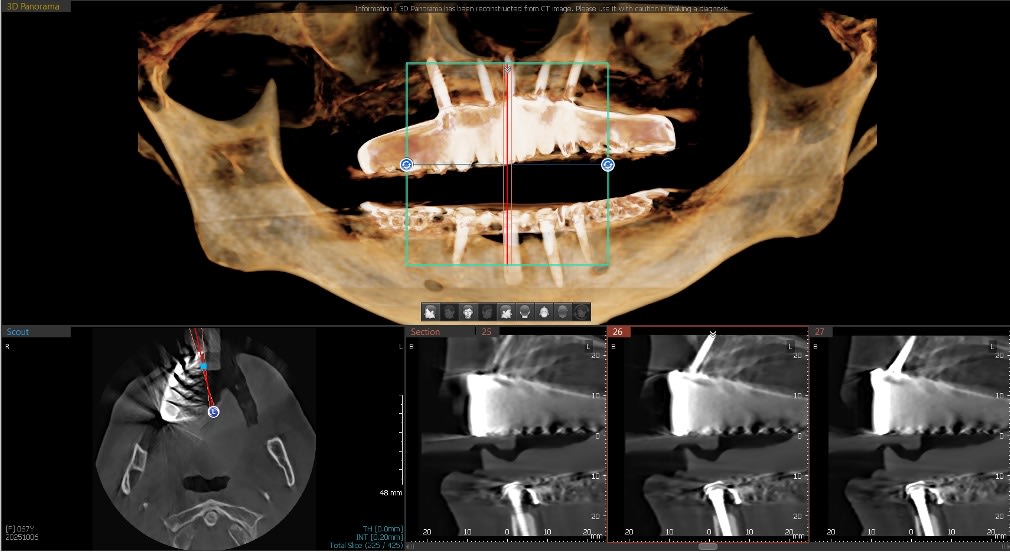

A 67-year-old female patient had a chief complaint of being unhappy with a previously fabricated full palate covered LOCATOR overdenture. The implant positioning was adequate, but the AP spread was not suitable to retain a palateless overdenture nor a fixed implant prosthesis. Five implants had apparently been placed previously but the maxillary right implant had not integrated properly and was removed prior to her evaluation in this practice. There were no significant health issues or medication concerns. She requested “permanent teeth” to improve her quality of life, function, and esthetics. The periodontal health around the existing dental implants was good, with no significant concerns. Figure 1 illustrates the esthetics created by the recently made maxillary and mandibular LOCATOR overdentures. The dentures provided some increased stability and function, but the patient’s concern was that they were not what was promised (Figure 2). CBCT analysis indicated some compromised bone contours where the maxillary right posterior implant has been avulsed (Figure 3). A newly placed fifth dental implant was needed to support any fixed prosthesis in this compromised edentulous arch. A new 3.5 mm x 10 mm HT™ dental implant (Glidewell, glidewelldental.com) was strategically positioned in front of the large maxillary sinus to provide distal support for the final prosthesis (Figure 4).

The patient was so pleased with the function, esthetics, and retention and the elimination of the palatal coverage that she requested a mandibular LOCATOR FIXED® restoration to replace the existing LOCATOR overdenture. Figure 17 illustrates the removal tool of this fixed prosthesis. The instrument engages under the bridge’s distal extensions for removal. Final CBCT analysis indicated acceptable integration of the dental implants supporting the fixed prosthesis (Figure 18).